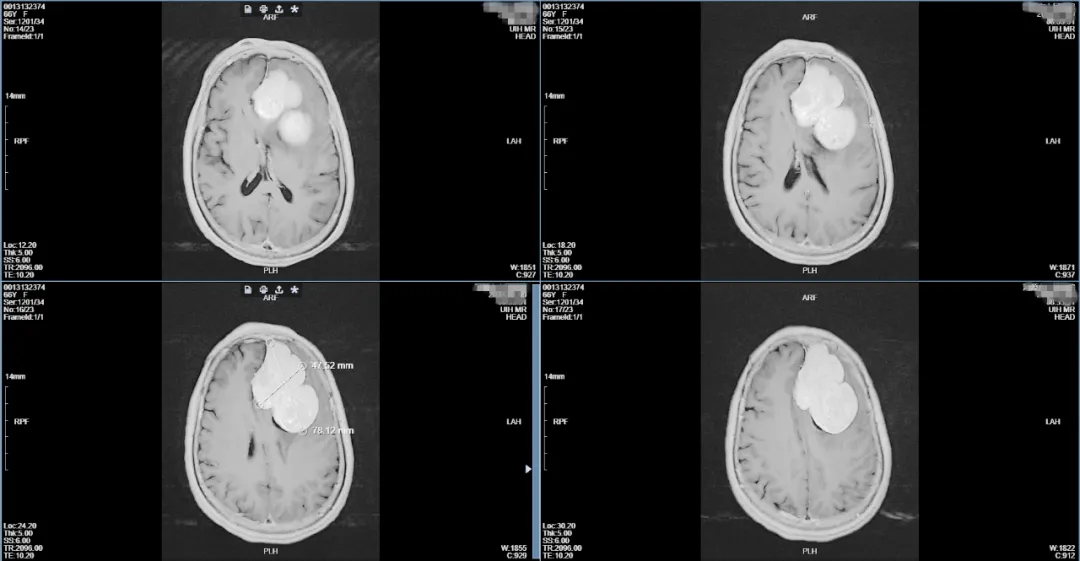

▲肿瘤大小约78mm×47mm×43mm

经过详细的颅脑增强磁共振检查发现吴阿姨为左侧额部巨大镰旁脑膜瘤,必须要尽快手术治疗,但肿瘤位于功能区旁且体积巨大,血供丰富,手术难度大、风险高,稍有不慎即可引起患者肢体偏瘫、失语、昏迷甚至危及生命可能。我院神经外科学科带头人王鹏副院长组织了术前多学科讨论,因肿瘤血供丰富,体积巨大,直接手术治疗面临术中失血多、手术时间长等困难,最终决定由神经外科介入团队先行介入栓塞治疗后再进行开颅脑膜瘤切除术。